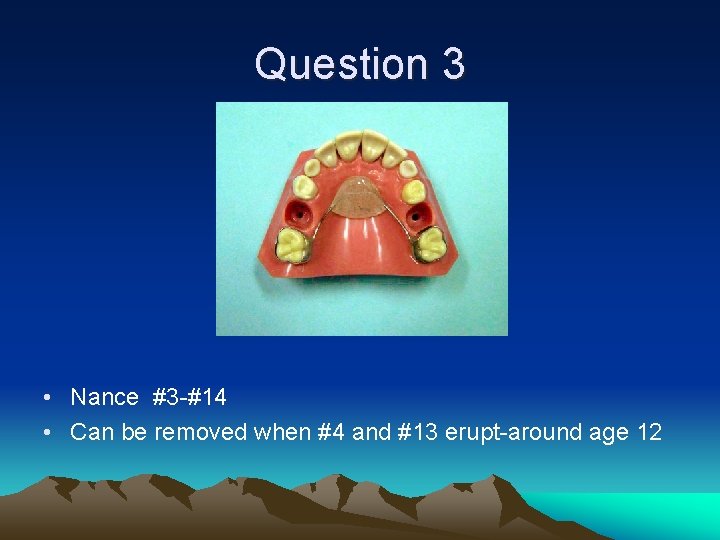

Question 3 • Teeth #A and #J extracted. Patient 8 -9 y. o.

Question 3 • Nance #3 -#14 • Can be removed when #4 and #13 erupt-around age 12